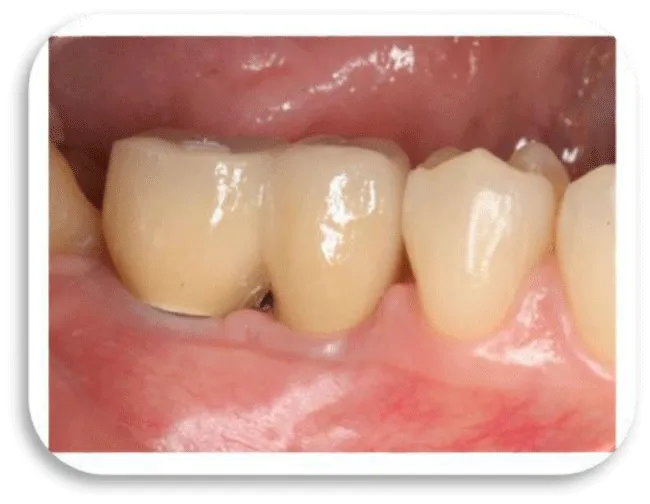

In peri-implant mucositis, the marginal gingiva in lightly bleeding bleeds. Gingiva is hyperemic and oedematous. The patient feels discomfort, mastication of food also leads to bleeding (Figure 4) [16].

With the progression of the peri-implant mucositis, the soft tissue condition around the dental implant is aggravated. Bone tissue destruction begins inside the alveolar bone around the implant itself, causing bone resorption. This process is irreversible in relation to peri-implant mucositis that is a reversible process (Figures 5-7) [17].